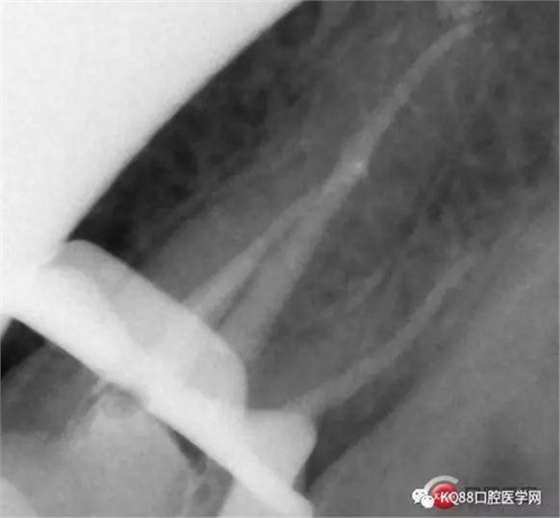

一個(gè)上6,常規(guī)的拍片,同上面的方法,根管口定位,乍一看三個(gè)根管,但是仔細(xì)研究,發(fā)現(xiàn)近中頰根,兩個(gè)根管口的C型根管,心理明了以后開始常規(guī)操作。

第一開髓后,只看見(jiàn)三個(gè)根管,于是進(jìn)行三個(gè)根管的預(yù)備,然后按照髓底解剖圖,進(jìn)行Mb2探查,近中頰根與腭根連線,遠(yuǎn)中頰根向其做垂直線,一般都在這條線附近,于是我開始去髓底白色鈣化,終于找到了Mb2,有鈣化,但是疏通后,到達(dá)根方,于是拍攝插針片。

四個(gè)根管成型,只是近中兩個(gè)根管融合為一個(gè),典型的C型根管。最后開始根充,射片。

充填完成。以此兩例根管治療,說(shuō)明的并不是完全技巧,更多的是態(tài)度,我的根管治療做的并不是很好,但是我一定會(huì)把態(tài)度端正起來(lái),希望同行們都能一起加油,利用手上最基本的設(shè)備,用心做好每一個(gè)根管。如有錯(cuò)誤,請(qǐng)多指證,謝謝!